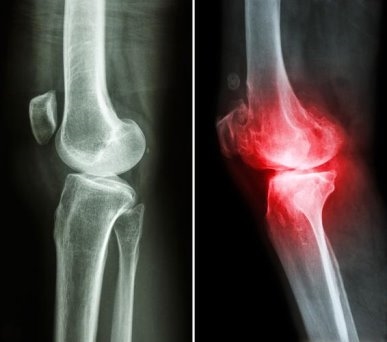

立冬將至,氣溫驟降、濕寒加重,不少人的關(guān)節(jié)開始“鬧脾氣”,酸脹疼痛、僵硬發(fā)麻,甚至活動(dòng)時(shí)還會(huì)發(fā)出摩擦聲,陰雨天不適感更甚。這其實(shí)是關(guān)節(jié)軟骨磨損后,骨關(guān)節(jié)炎發(fā)出的預(yù)警信號(hào),若不及時(shí)干預(yù),病情可能持續(xù)進(jìn)展。想要安穩(wěn)過冬、守護(hù)關(guān)節(jié)健康,選對(duì)干預(yù)方式很關(guān)鍵。而維固力這類OTC硫酸氨糖,便是臨床常用的骨關(guān)節(jié)炎治療藥物,憑借確切療效和高耐受性,成為不少人應(yīng)對(duì)秋冬關(guān)節(jié)不適的優(yōu)選。

骨關(guān)節(jié)炎是一種以關(guān)節(jié)軟骨磨損、破壞等為特征的慢性退行性疾病。當(dāng)失去了軟骨的緩沖,關(guān)節(jié)間直接摩擦,遇寒、受潮時(shí)就容易誘發(fā)炎癥。而氨糖是合成軟骨細(xì)胞的核心原料,也是構(gòu)成軟骨基質(zhì)與關(guān)節(jié)液的基礎(chǔ)成分。它不僅能修復(fù)受損軟骨組織,還可補(bǔ)充關(guān)節(jié)滑液,降低摩擦,同時(shí)通過抑制關(guān)節(jié)腔內(nèi)的炎癥因子,有效延緩骨關(guān)節(jié)炎的發(fā)展進(jìn)程[1]。

同時(shí),維固力能夠有效緩解關(guān)節(jié)不適這一點(diǎn),得到了世界頂級(jí)醫(yī)學(xué)期刊《柳葉刀》的證明。《柳葉刀》一項(xiàng)研究表明,治療膝骨關(guān)節(jié)炎時(shí),長(zhǎng)期服用維固力可顯著減輕關(guān)節(jié)疼痛程度約4倍[3],提升關(guān)節(jié)功能指數(shù)約2倍[4],延緩關(guān)節(jié)間隙變窄的程度約4倍[5],從根源改善關(guān)節(jié)結(jié)構(gòu),延緩關(guān)節(jié)磨損。